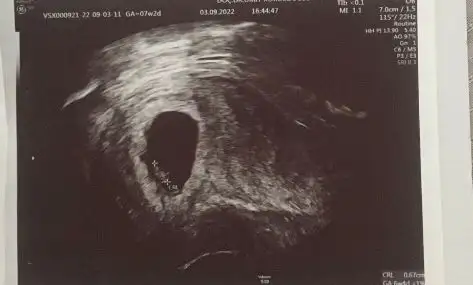

İki kızım var bubub cinsiyet nedir acaba bilgisi olan varmı![]()

Bnm bebegimede yorum yapabilirmisinizVajinalsa tam tersi oluyor kız olabilir

Burda size yorum yapmıştım aslında.Sizinkini erkeğe benzettim bu arada kese şekillerimiz çok benziyor cinsiyetleri aynı olursa şaşırmam![]()

Hiç bilmiyorum doktor söylemedi hayırlısı sağlıklısından olsun inşallah benimde bir kizim var bu arada 8 haftalık gebeyim ama usg de biraz küçük çıkıyor bebek kızımda tam tersi hep büyük çıkardıAyy görmedimins ikimizinde sağlıkla erkek olur ama burda plesanta nerde eğer soldaysa erkek sagdaysa kız sizin kaç haftalik